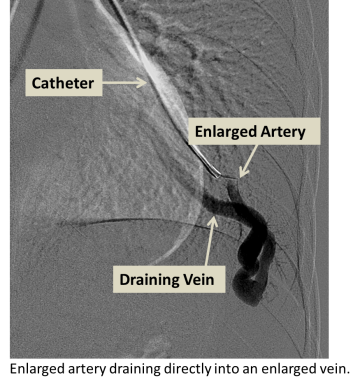

Enlarged artery draining directly into an enlarged vein

Arteriovenous malformations (AVMs) refer to arteries and veins with abnormal connections between them. In the lungs, arteries first carry blood from the heart to smaller arteries which then feed into even smaller vessels called capillaries. Capillaries, which are within organs, slow down blood flow and allow for nutrient and gas exchange between the blood and organs. Veins carry blood away from capillaries and back to the heart.

In the presence of an AVM, the arteries and veins are directly connected without intervening capillaries, reducing gas exchange and causing decreased oxygen levels and shortness of breath, especially with exertion. The abnormal arteries and veins in an AVM often have weak walls, and bleeding into the lung can result.  Clots or bacteria in the lung circulation that would normally get trapped in small capillaries can pass through the AVM to the blood vessels of the brain and cause stroke or brain abscess.